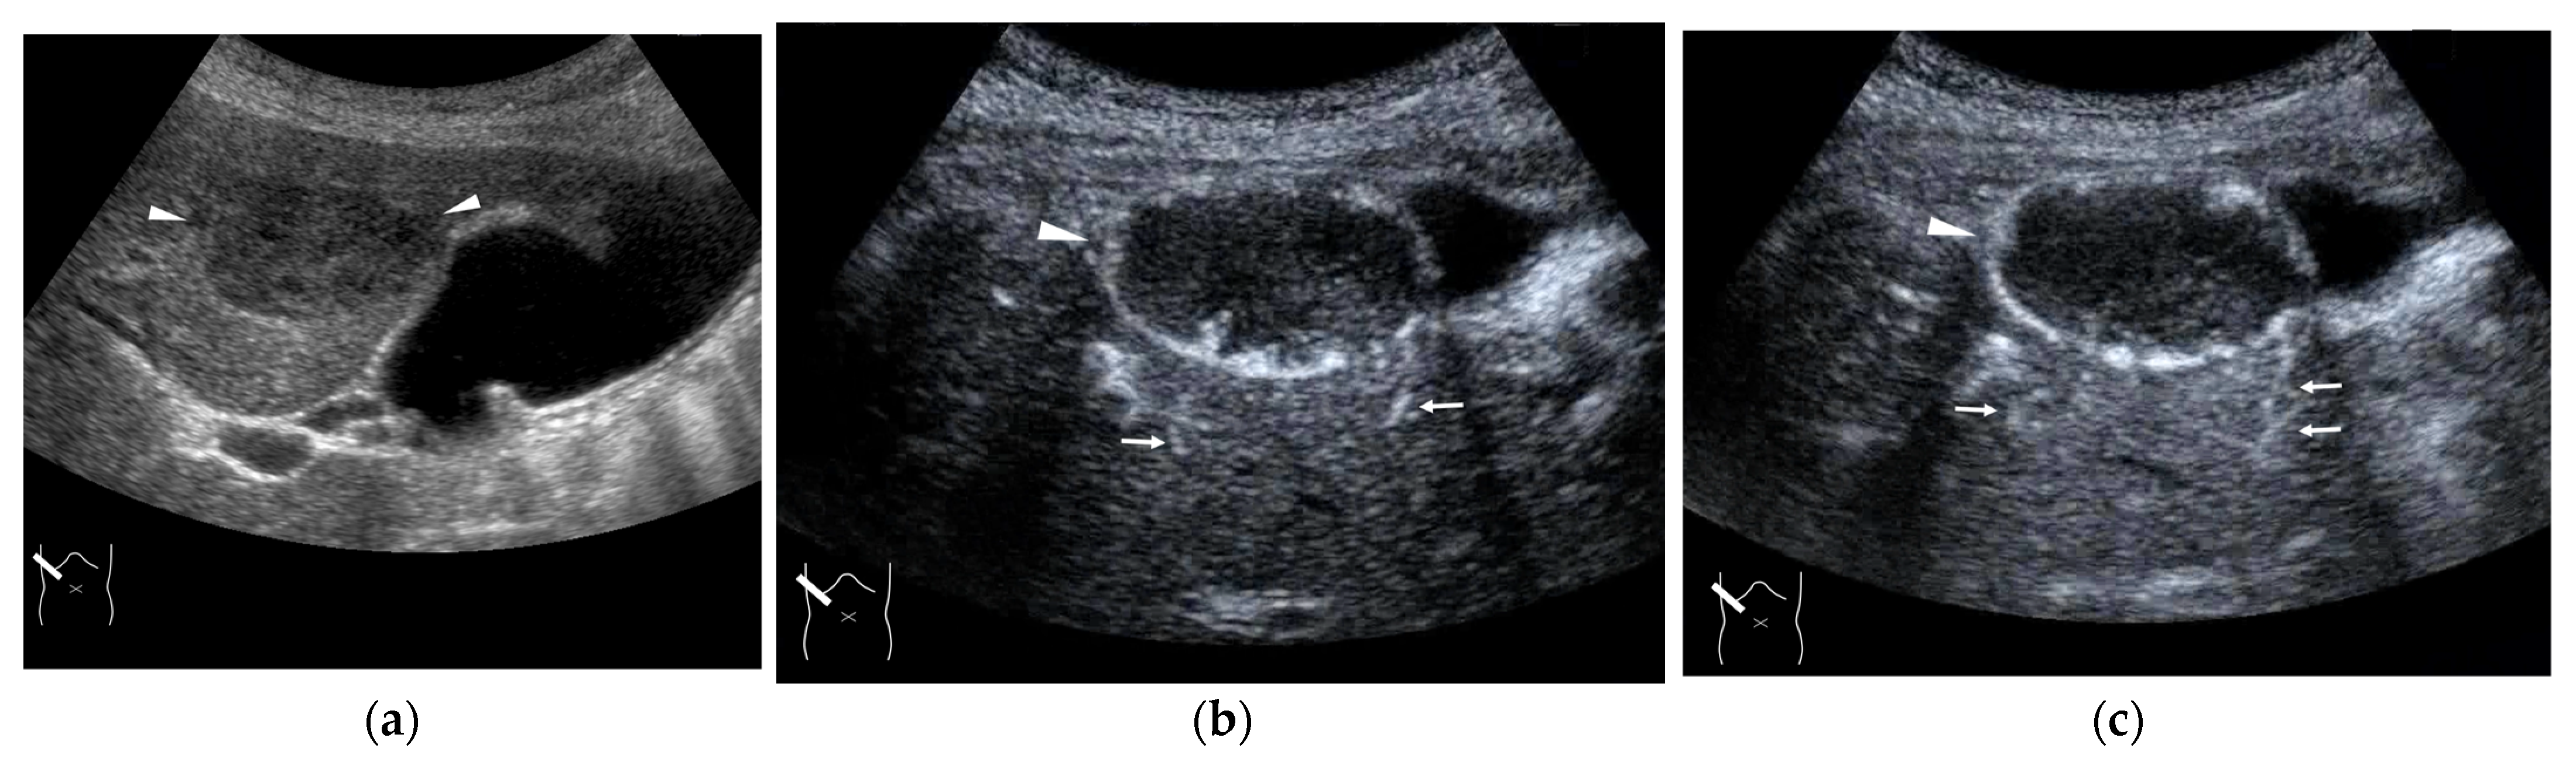

4.3. Budd–Chiari Syndrome

4.2. Congenital P-V Shunts

3. HV Hemodynamic Changes in Liver Tumors